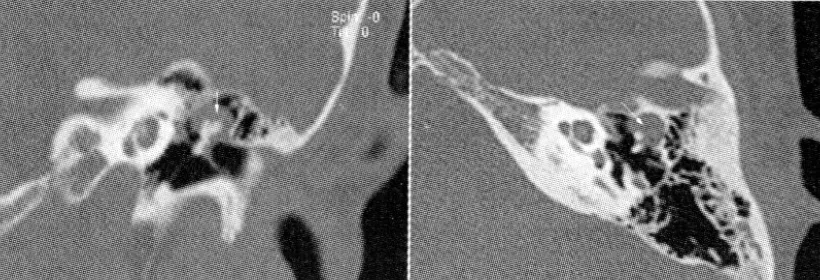

【107-1 醫學(六) 第19題】有關聽神經瘤(acoustic neuroma)的臨床敘述,下列何者錯誤?